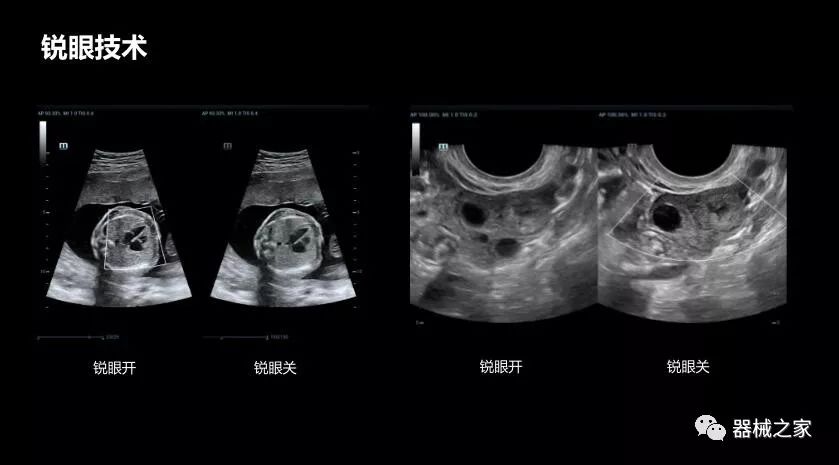

• 銳眼技術

做胎兒心臟檢查的時候,如果是聲窗不好的孕婦,很難看清胎兒心腔 。女媧Resona 8的銳眼技術能很好的優(yōu)化心腔內的噪聲,讓胎心結構完美的呈現(xiàn)。